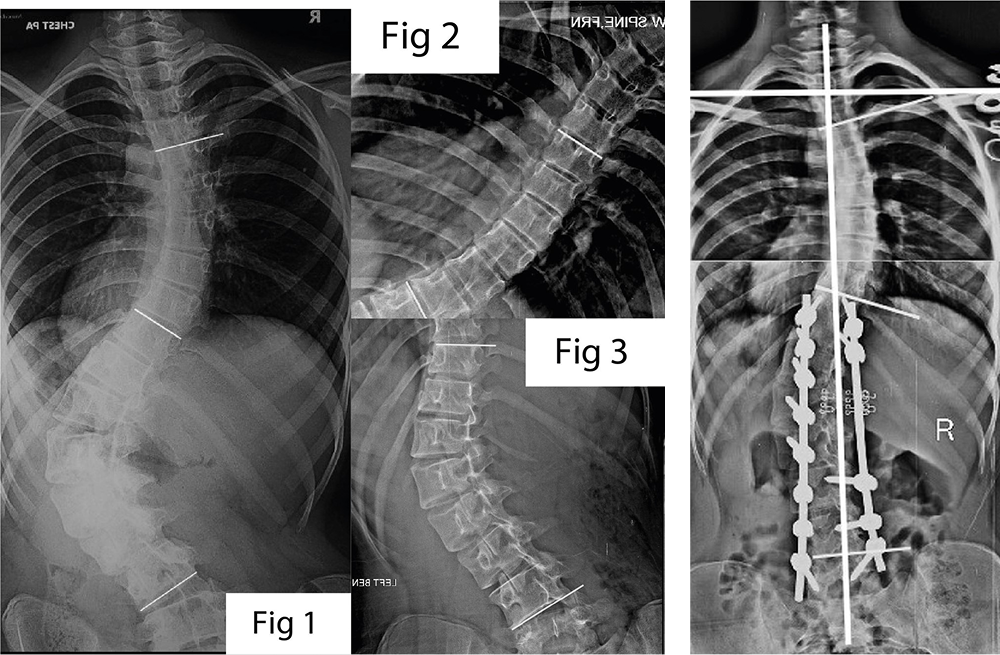

Case 1: Scoliosis in a Young Patient – Treating Only What Is Needed

A 14-year-old girl came to Sattvik Spine with a visible curve in her back. Her posture had changed slowly over time. Tests showed two curves in her spine:

- A larger curve in the lower back

- A smaller curve in the upper back

The condition was not just about appearance. If ignored, it could affect balance, walking, and confidence.

Understanding the Real Problem

Instead of treating the entire spine, Dr. Yogesh K. Pithwa carefully studied how the spine moved. He noticed that the lower curve was the main cause of imbalance. The upper curve had the ability to correct itself once the lower part was treated.

This careful observation helped avoid unnecessary surgery.

The Surgical Decision

Only the affected part of the spine was treated. This approach is called selective fusion. It helps:

- Protect healthy parts of the spine

- Reduce stiffness after surgery

- Lower the physical and emotional burden on the patient

This reflects the values of minimally invasive spine surgery, where preserving natural movement is always a priority.

The Result

After surgery:

- The spine became well balanced

- The patient stood straight

- Movement was smooth and natural

- Long-term results remained stable

This showed that doing less can sometimes do more.